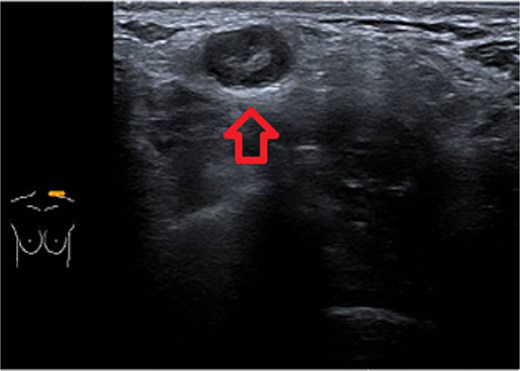

One week later, the patient reported a new lump in the left supraclavicular area. Examination revealed a 2 × 3 cm, nontender, mobile mass, confirmed by ultrasound to be silicone deposition (Figs 3 and 4). Increased breast swelling and lymphadenopathy were attributed to implant rupture and silicone migration.

Typical snowstorm appearance of supraclavicular silicone lymphadenopathy.

Imaging is a vital first step in the diagnostic evaluation of patients with lymphadenopathy. Ultrasound is the primary tool for diagnosing silicone lymphadenopathy, while additional imaging techniques, including MRI, CT, and mammography, can offer further insights for confirmation and detailed assessment of lymphadenopathy [11]. The sensitivity and specificity of using ultrasound to diagnose silicone lymphadenopathy by identifying the snowstorm sign have been reported as 87.5% and 100%, respectively [11]. In our case, the ultrasound typical snowstorm appearance was enough to make the diagnosis. Even though if any clinical concern about malignant or infectious process, cytological or histological evaluation is mandatory to confirm the diagnosis. Also in patients with previously treated breast cancer and having the implant as reconstructive measure; concerns about disease recurrence should be carefully considered.